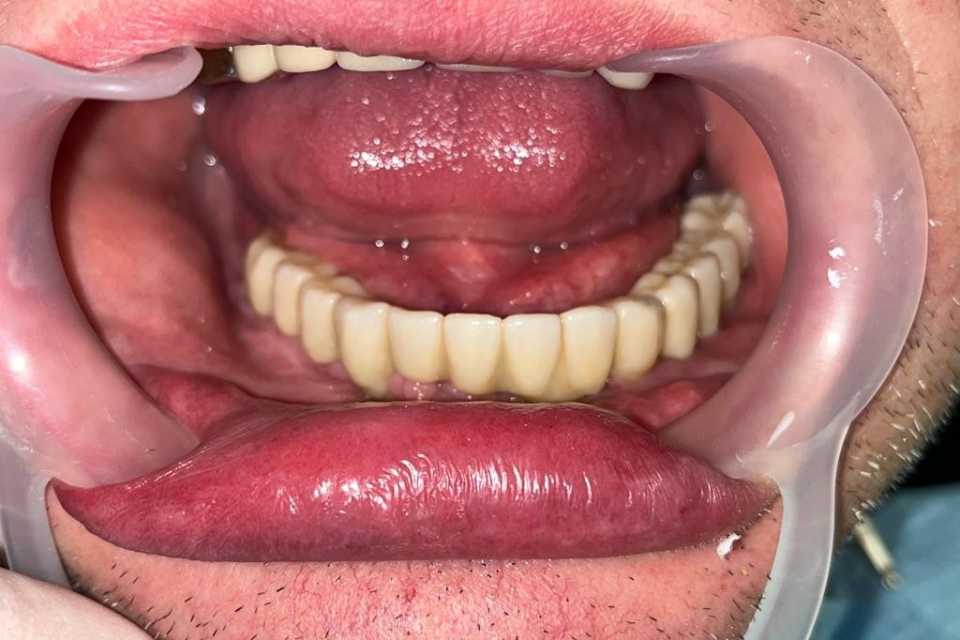

Lucrare fixă înșurubabilă pe implanturi

Cazul 53: All on 6

Pacient în vârstă de 45 de ani, vechi purtator de proteza totală inferioara s a prezentat cu dorința de a efectua o lucrare pe implanturi fixa.

Cazul a fost unul foarte dificil prin prisma resorbtiei osoase în zonele laterale mandibulare și ale patologiilor asociate ale pacientului, prohibitive pentru adiții osoase.

Astfel, am optat, impreuna cu pacientul, pentru 6 implanturi Straumann BLX Roxolid, inserate lateral de nervul alveolar inferior, metodă care ne-a ajutat sa evitam procedura de aditie osoasă, pe care am realizat o lucrare fixa insurubabila din Zirconiu.

Rezultatul final a fost pe masura așteptărilor pacientului.